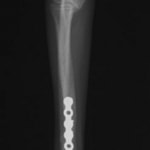

脛骨骨折 : 症例1 | 症例2 | 症例3 | 症例4 | 症例5

当院ではAdvanced Locking plate system(ALPS)と、Locking compression plate system(LCPS)という骨接合法で骨折症例の治療を行っています。

LCPは、スクリュー(ネジ)とプレート(金属の板)をロックする特殊な構造により骨折部位を固定する新しい世代のプレートシステムです。ひとつのホールでロッキングスクリューとスタンダードスクリューの使用を選択できるユニークな構造をしているため、骨折断端間の圧迫を目的とした従来型プレート固定法に加え、高い角度安定性を有するロッキングスクリューを用いた固定法の選択が可能です。従来のプレートシステムでは困難だった部分の骨折や癒合不全の症例に高い治療効果をもたらします。